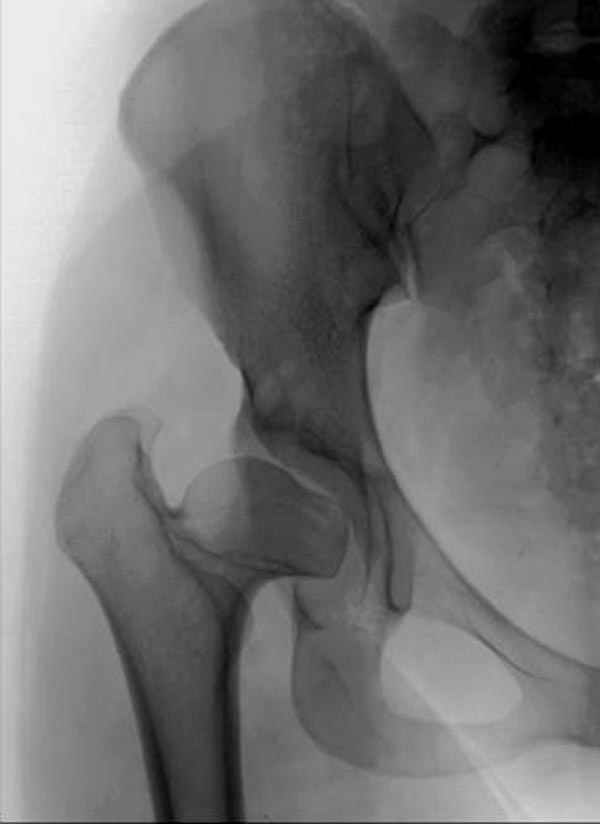

It appears that this patient has bilateral congenital hip displasia, as presented on the radiographs. As shown, the problem involves both sides of the hip joint: the acetabulum and proximal femur.

This patient is noted to have a very vertical joint surface orientation, as well, with retroversion of the acetabulum.

In a hip with normal version, (on discussion list) Hip Pain (Dr.Kullerkann) the lines connecting the anterior and posterior acetabular wall as seen on an AP radiograph usually intersect at one point near the superior and lateral portion of the acetabulum. As an example of an abnormal hip, a patient with a retroverted acetabulum will show the figure 8 pattern, with the two shadows crossing over the femoral head. In this particular patient, again it appears that there is a significant amount of retroversion of the acetabular wall, as the anterior wall appears to be more anteriorly displaced than in a normal hip.

In this patient, it appears that addressing either the femur or the acetabulum will be insufficient to help correct this patient’s problem. It would be necessary to approach both sides of the hip joint to correct the hip dysplasia.

Pic. 1-5 preop plan; 6-8 similar case